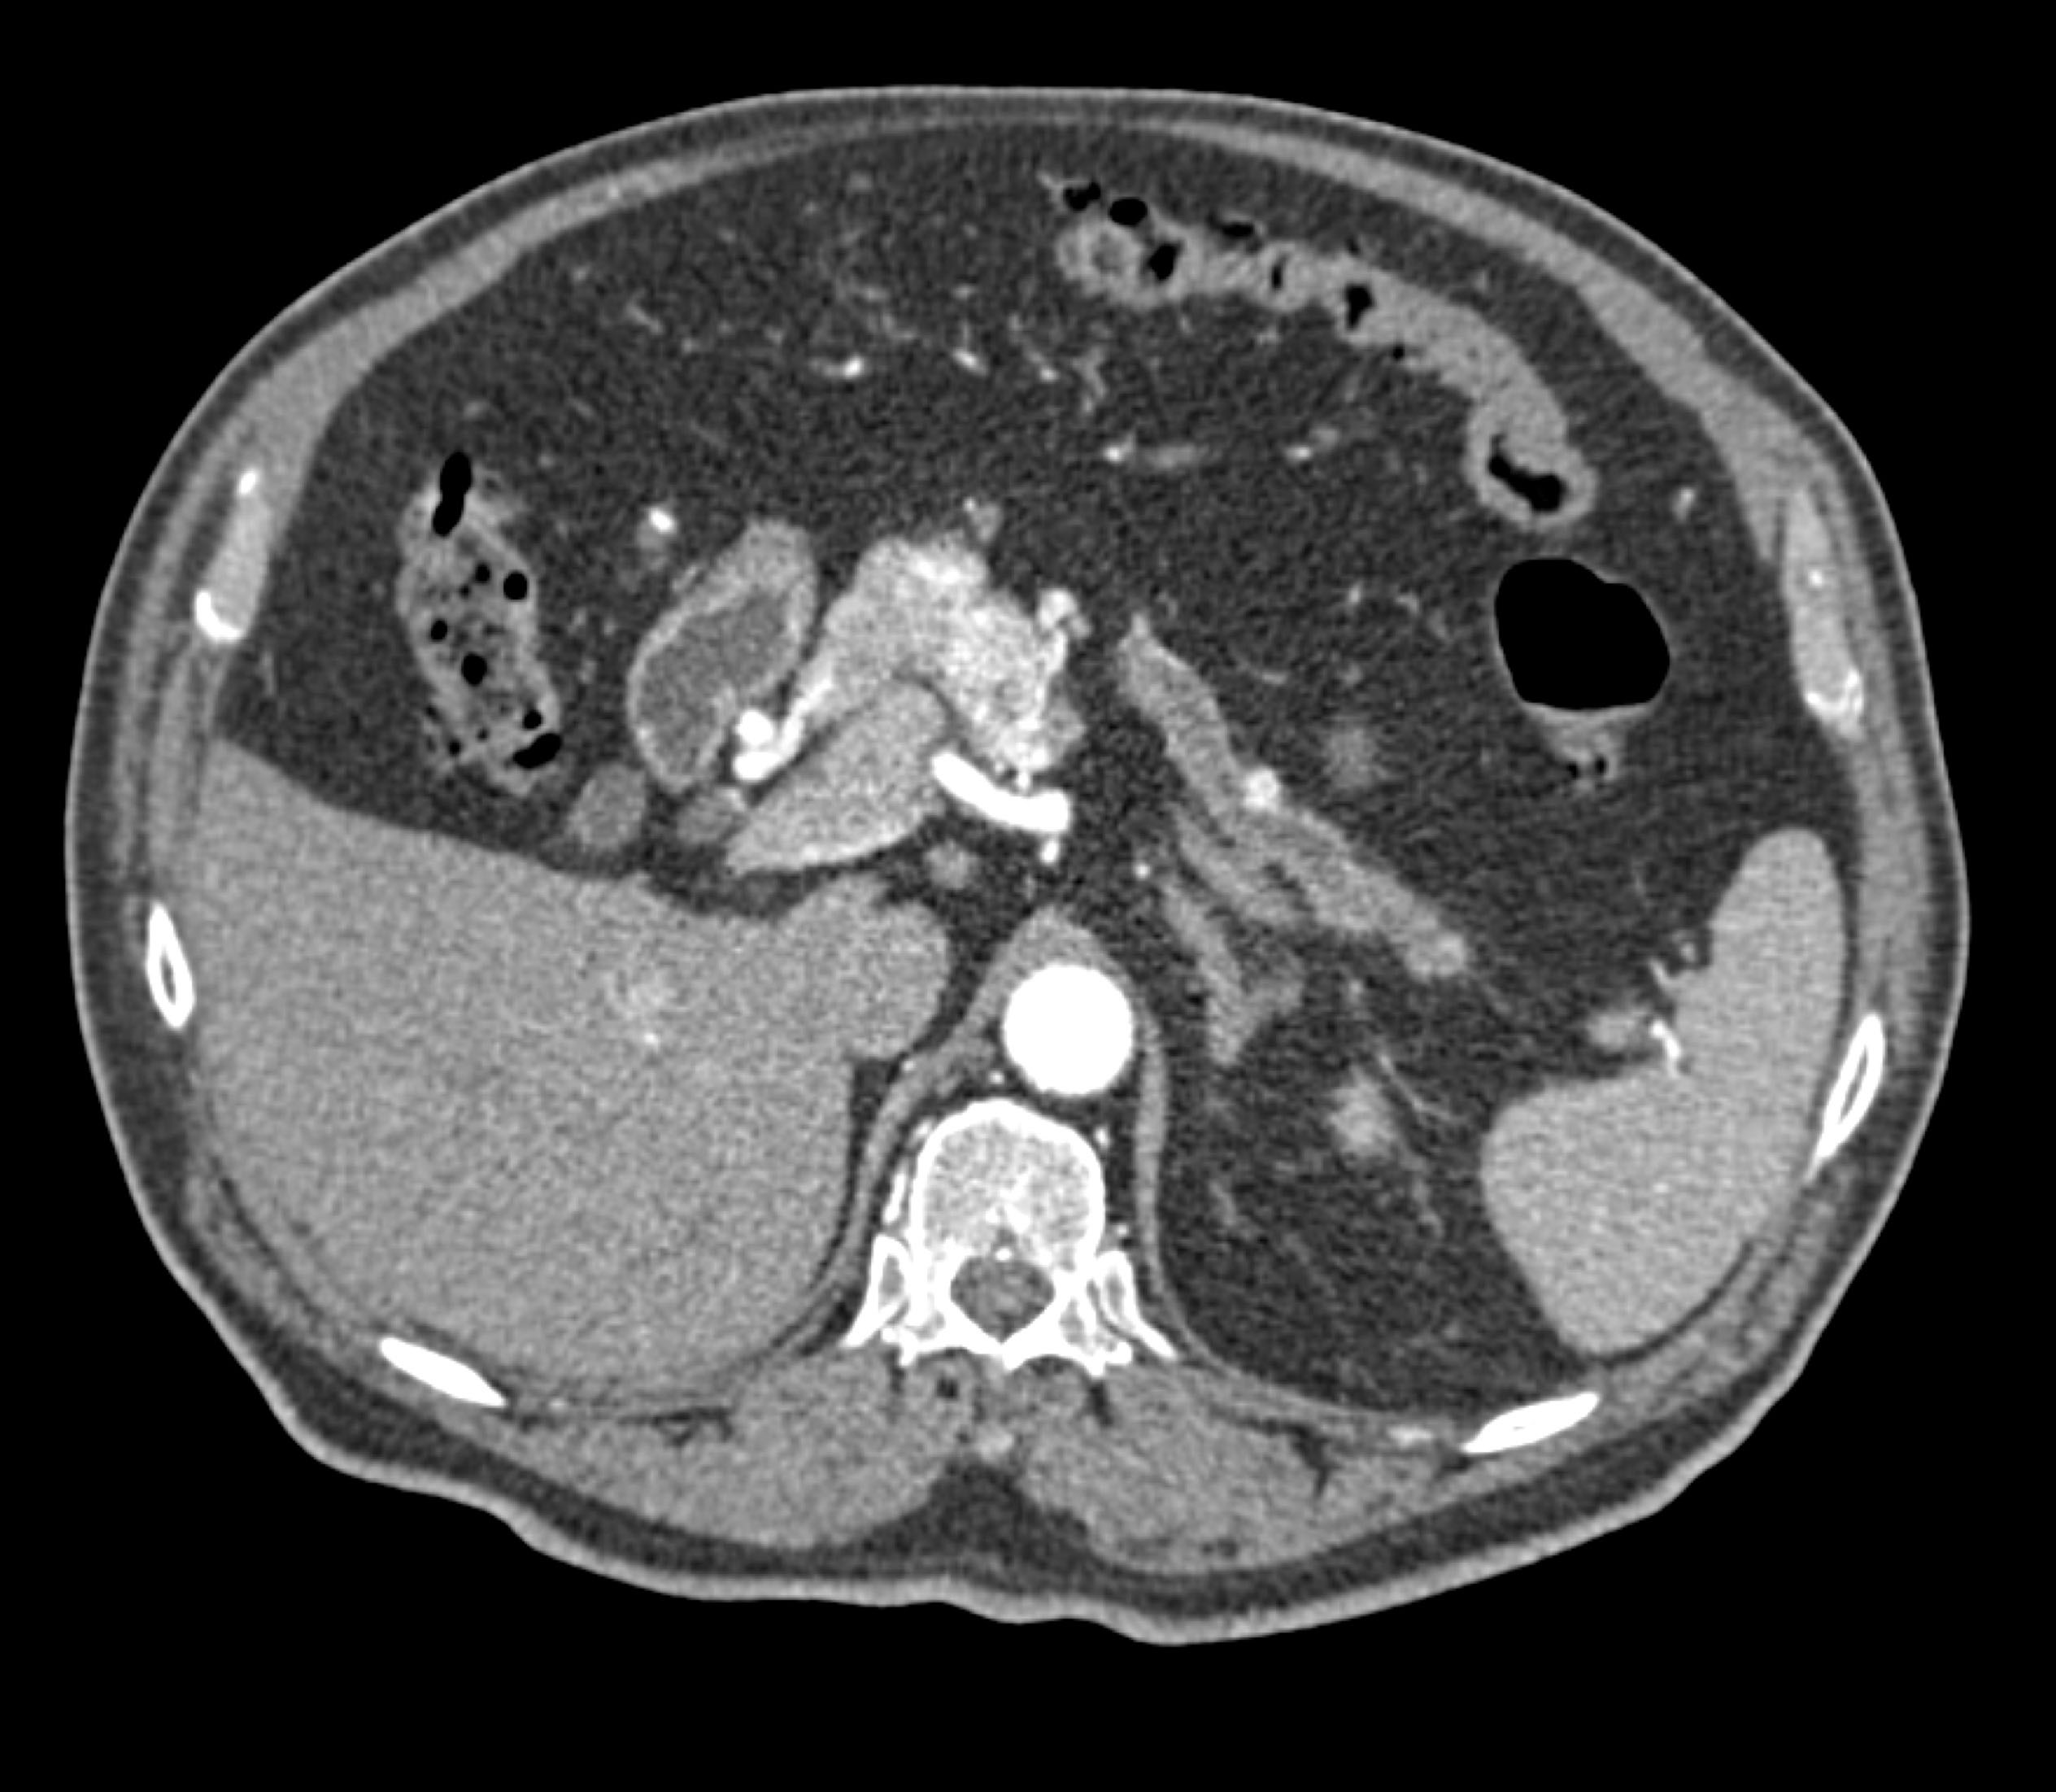

- Evaluate the CT images of each question carefully.